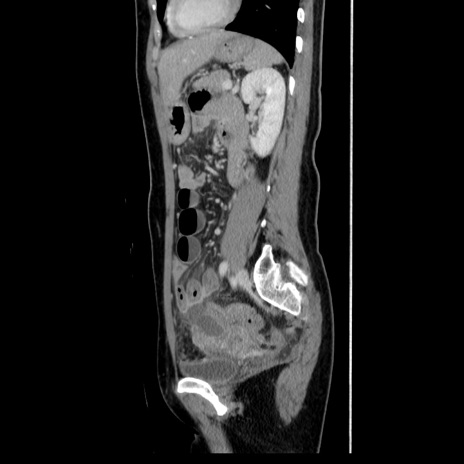

症例39(矢状断像)

【症例】40歳代女性

【主訴】上下腹部痛

【現病歴】2日目から下腹部痛あり。夜間は痛みで眠れなかった。昨日より上腹部痛と下痢が出現。臥位で痛みは軽快したため、休んでいた。本日になって臥位でも立位でも痛みが強くなってきたため救急要請。

【既往歴】子宮内膜症

【身体所見】部:平坦・軟、左上下腹部に圧痛あり、反跳痛あり。

【データ】WBC 21800、CRP 26.78

CT